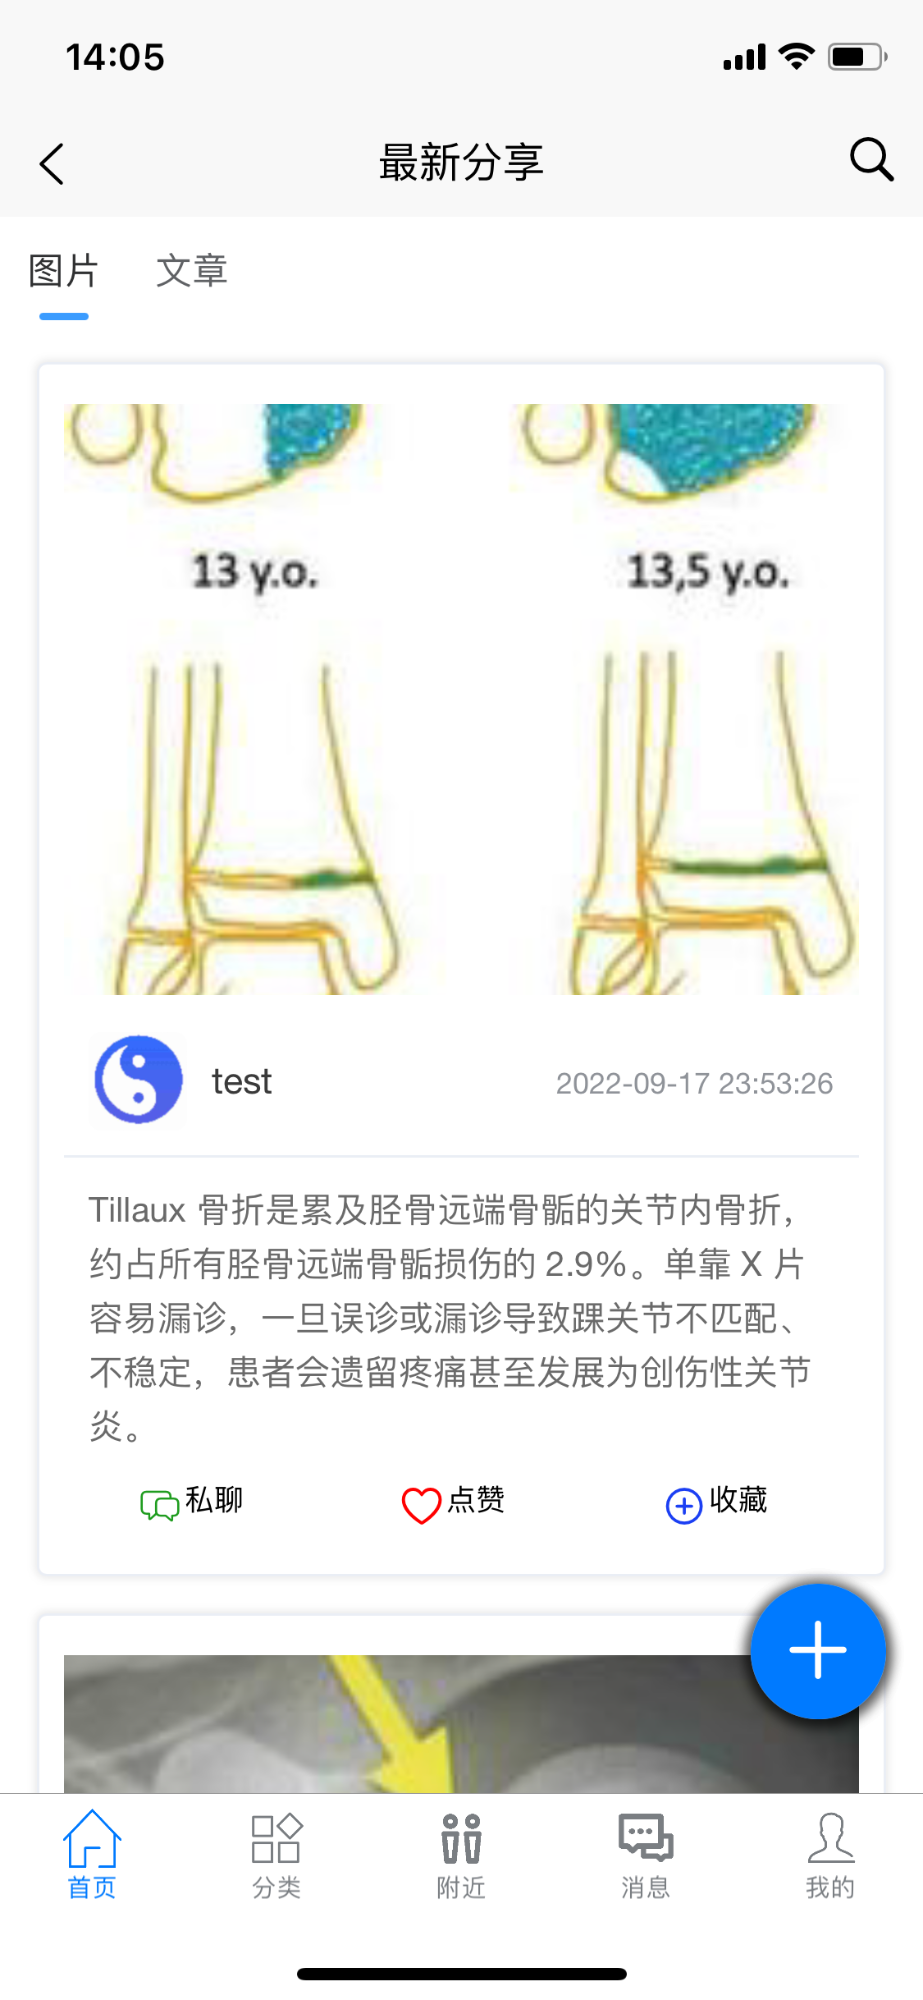

主页

显示最新分享的图片及精华文章。可对喜欢的予以点赞及收藏。